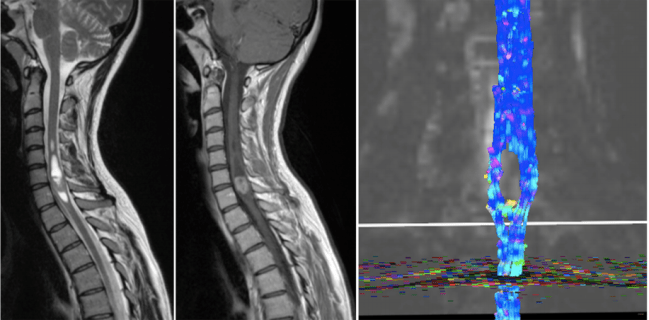

From [4]. Diffusion MRI can aid in surgical planning. Left: MRI scan showing a tumor in the lower cervical spinal cord. Middle: Same MRI image after contrast enhancement. Right: Diffusion MRI shows displacement of white matter around the tumor.